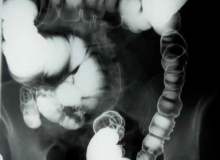

Kapsül endoskopi, sindirim sisteminizin resimlerini alabilmek için ince ve kablosuz bir kameranın kullanıldığı bir işlemdir. İşlem sırasında içine endoskopi kamerası yerleştirilmiş olan, genellikle vitamin büyüklüğünde bir kapsülü yutarsınız. Kapsül